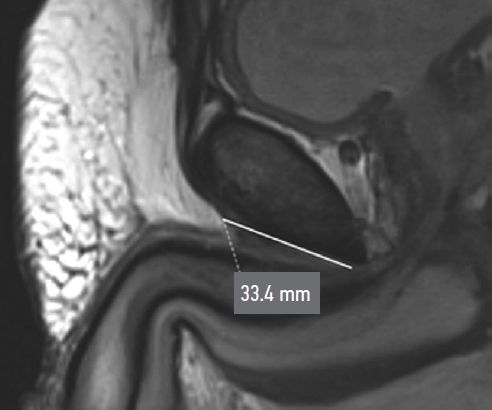

During preoperative assessment, penile length was recorded in both the flaccid and stretched states (median: 6.75 cm and 12 cm, respectively). Penile length in erection was measured by the patient at home (median: 12.5 cm). All patients underwent pelvic magnetic resonance imaging (MRI) to assess the topographic anatomy of the penile suspensory apparatus preoperatively. The following parameters were recorded: length and width of the suspensory ligament (median: 2.7 cm and 1.4 cm, respectively), thickness of the subcutaneous fat layer (median: 2.85 cm), angle of ligament divergence in the frontal plane (median: 65.8°), and the angle between the corpora cavernosa and the pubic symphysis (median: 17.42°) (Fig. 1–Fig. 5).

Fig. 4. Divergence angle of the ligament fibers.